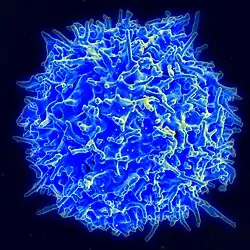

T Cell | Lymphocyte | T Cell |

|

8-10 |

|

[4][17] |